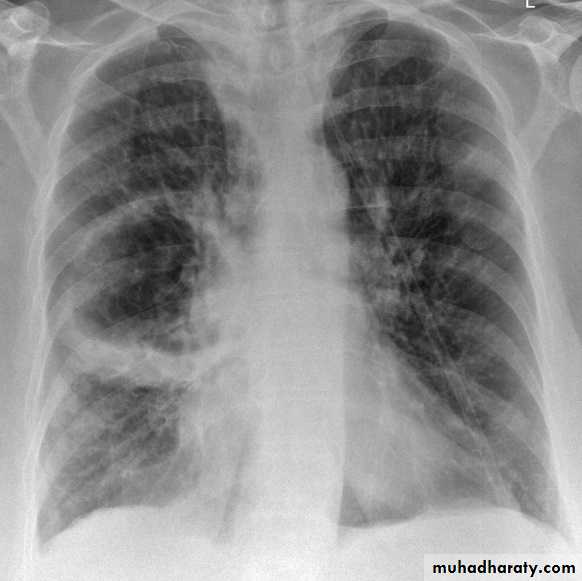

Right upper lobe collapse has distinctive features, and is usually easily identified on frontal chest radiographs .

Radiographic features

Chest radiograph

Collapse of the right upper lobe is usually relatively easy to identify on frontal radiographs. Features consist of :

increased density in the upper medial aspect of the right hemithorax

elevation of the horizontal fissure

loss of the normal right medial cardiomediastinal contour

elevation of the right hilum

hyperinflation of the right middle and lower lobe result in increased translucency of the mid and lower parts of the right lung

right juxtaphrenic peak

A common cause of lobar collapse is a hilar mass. When a right hilar mass is combined with collapse of the right upper lobe, the result is an S shape to elevated horizontal fissure. This is known as Golden S sign .

Non-specific signs indicating right sided atelectasis are also usually present including:

elevation of the hemidiaphragm

crowding of the right sided ribs

shift of the mediastinum and trachea to the right